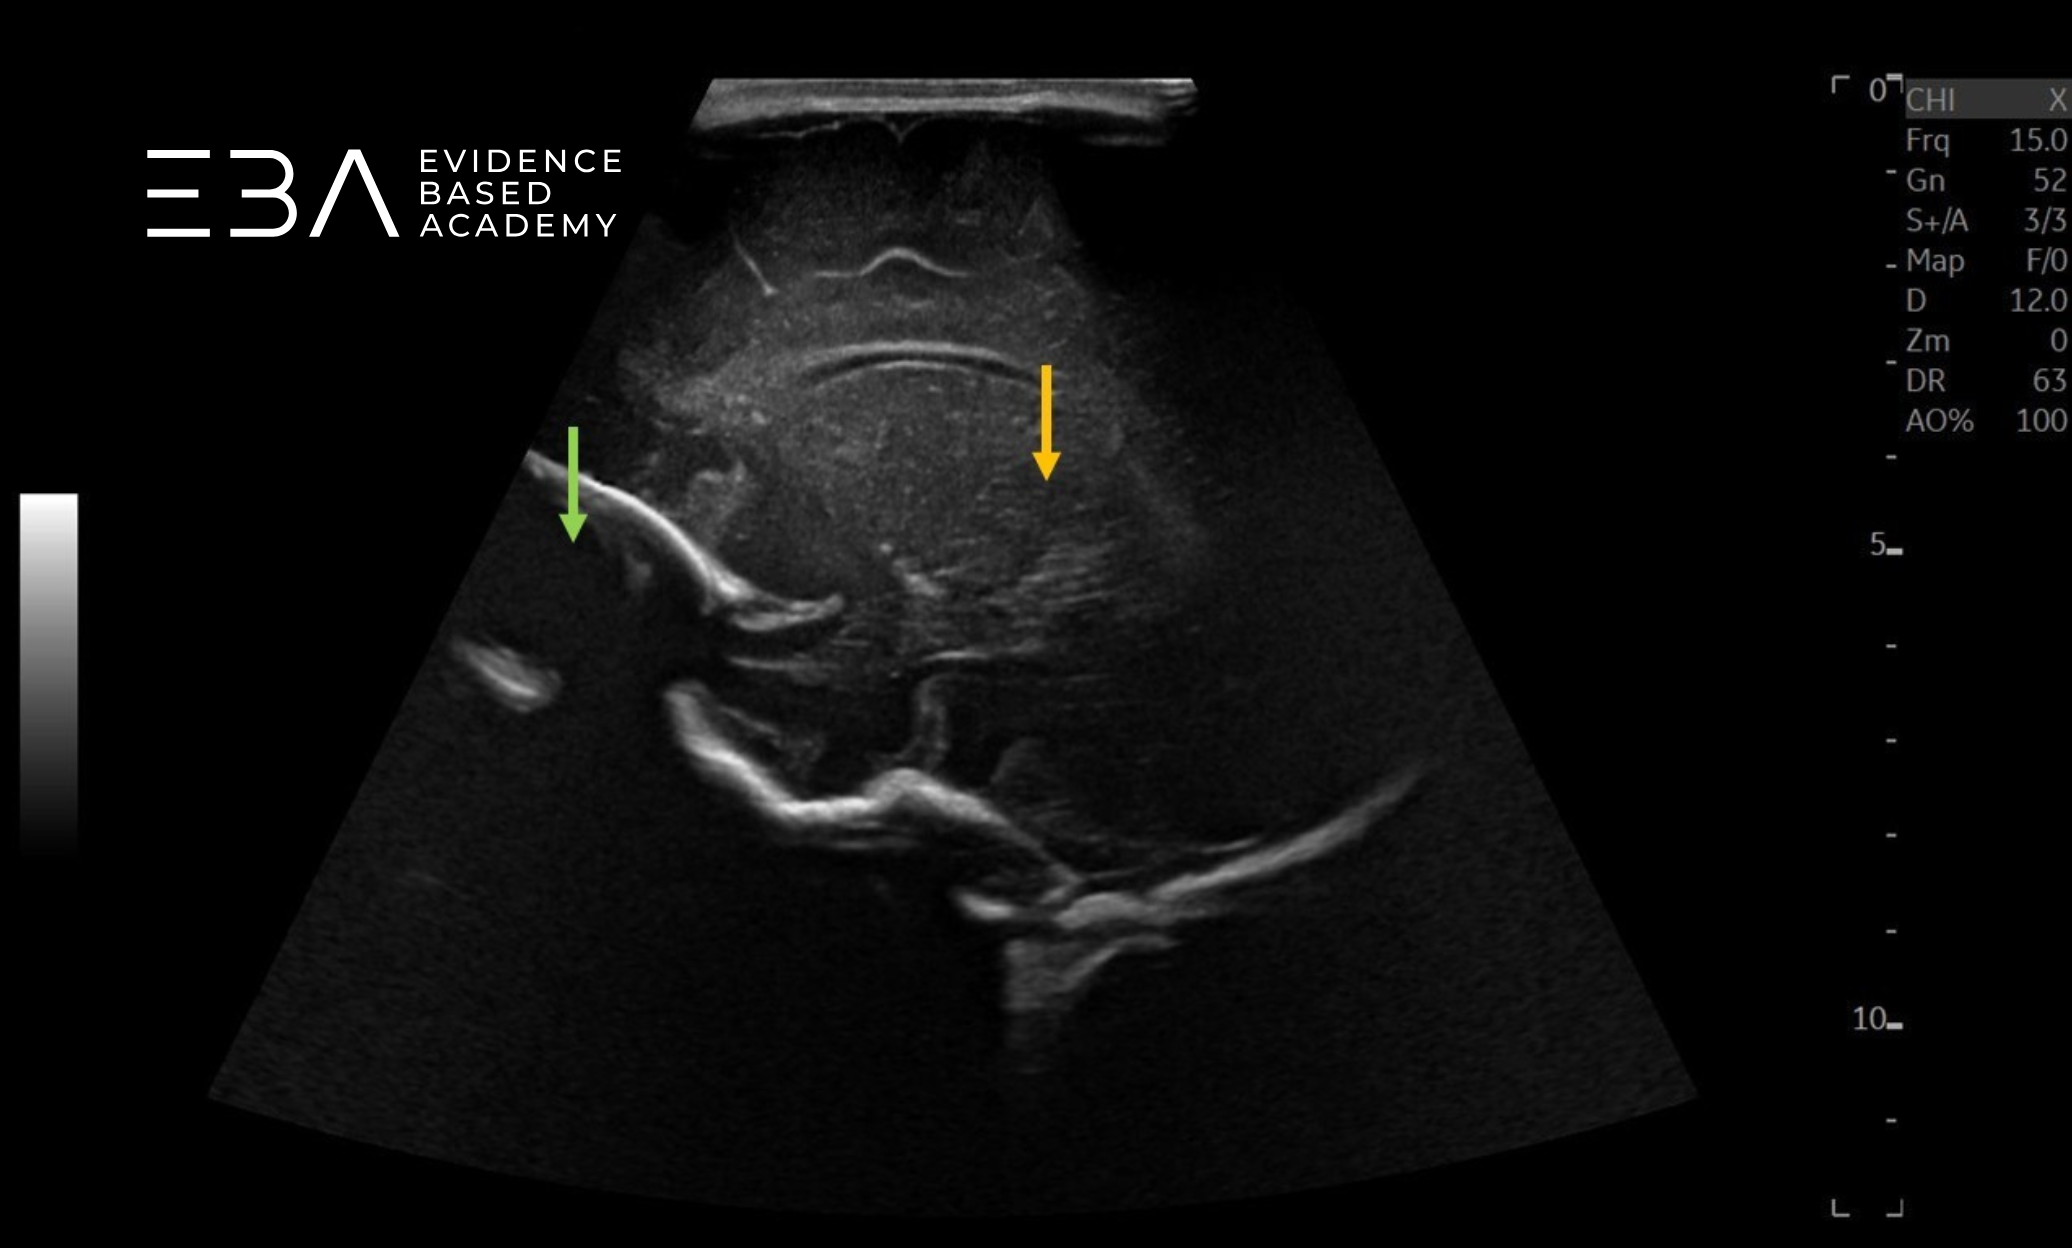

zdj. 5b

Głowica sektorowa – badanie przez łuskę kości skroniowej. Strzałkami zaznaczono konary mózgu.